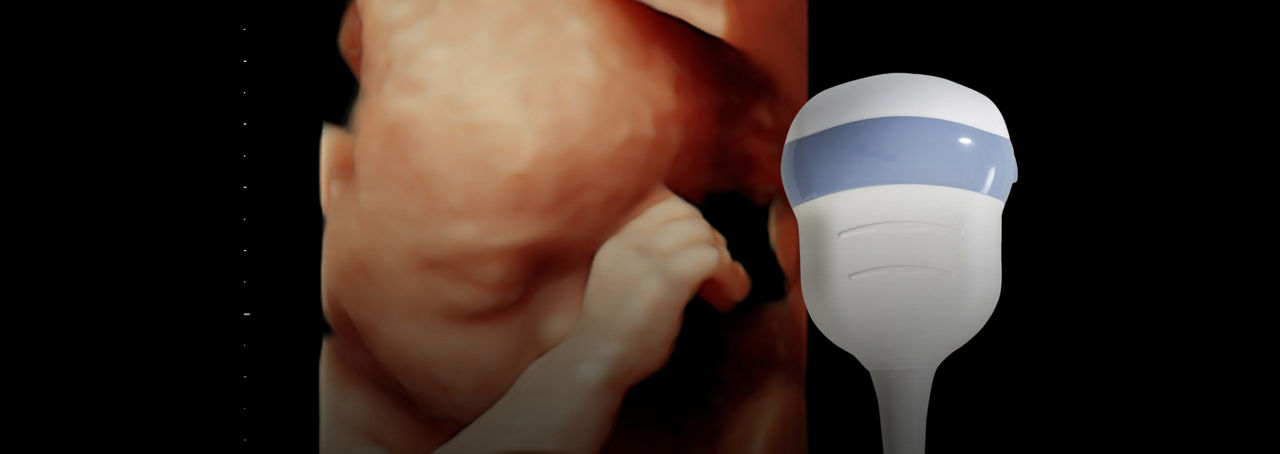

Effortless Imaging

Capture images quickly and confidently with our Voluson Core Architecture. Just place the transducer and start scanning to acquire images with minimal manipulation.